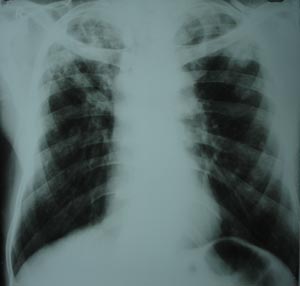

Bilateral pulmonary tuberculosis

Both upper zones & right mid zone reveal fibronodular opacities.